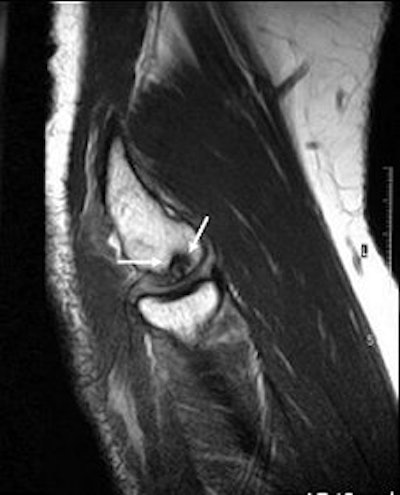

|  |

| Sagittal MRI of JOCD on 1.5-tesla scanner. Protocol included FSE and T2-weighted imaging (TR/TE 3500/55). Image courtesy of Dr. Nancy Major, Duke University Medical Center, Durham, NC. |